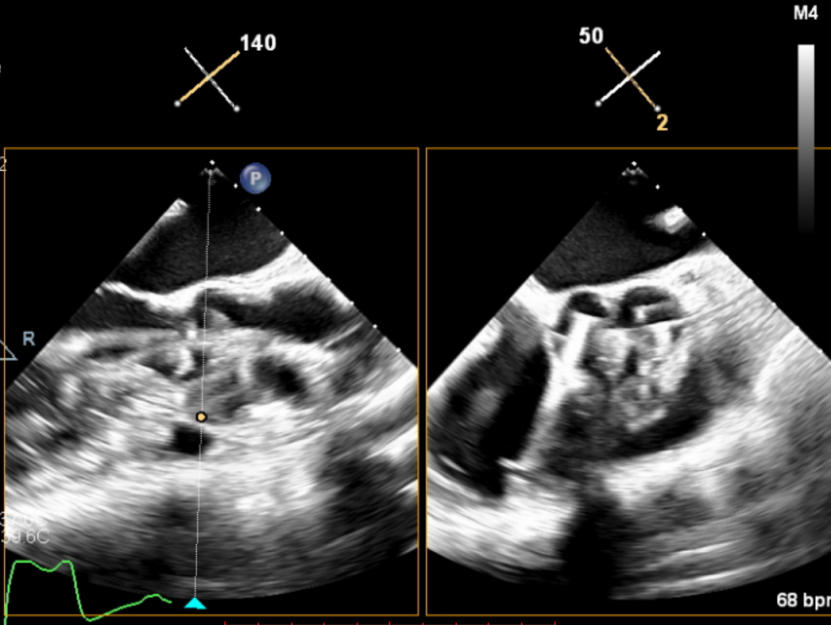

输送器顺利跨瓣,释放外鞘管,开始定位释放,超声评估可见定位件入窦可,后释放内鞘管,打开瓣架,瓣叶活动良好,无瓣周反流,综合考虑瓣膜稳定良好,脱钩释放。

(输送器跨瓣)

(瓣膜打开定位件)

(定位件入窦)